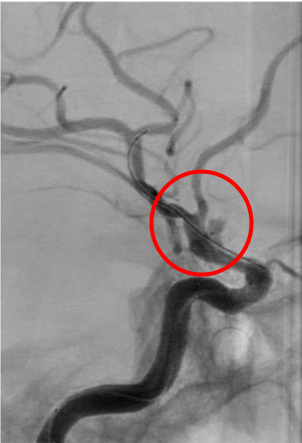

破裂内頚動脈瘤

術前の造影写真です。〇内に脳動脈瘤が造影されています。

術後の造影写真です。主幹動脈は温存できており、動脈瘤は造影されなくなっています。